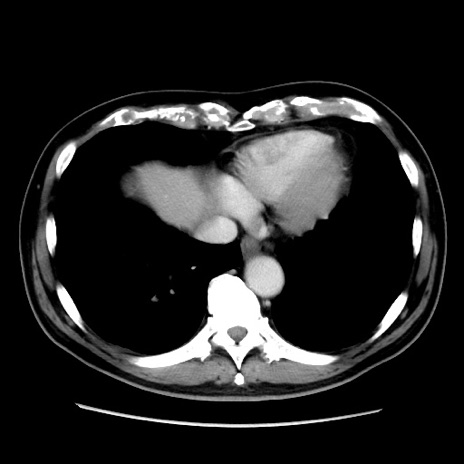

冠状断像

【症例】 70歳代男性

【主訴】 腹痛、嘔吐

【現病歴】 約1ヶ月前より間欠的に腹痛と嘔吐あり、当院消化器内科を受診したところCTで多発する肝臓のLDAを指摘され、精査中であった。以降は消化器症状は安定していたが、2日前より嘔気と腹痛があり、同日より排便・排ガスが消失した。改善認めず、 本日、救急外来を受診した。

【既往歴】 大腸ポリープ切除後。

【身体所見】意識清明・会話良好、BT 36.3℃、BP 127/80mmHg、 P 80bpm、腹部:膨満あり、平坦・軟、上腹部正中および下腹部正中に圧痛あり、反跳痛なし、筋性防御なし。

【データ】WBC 7200、CRP 0.77